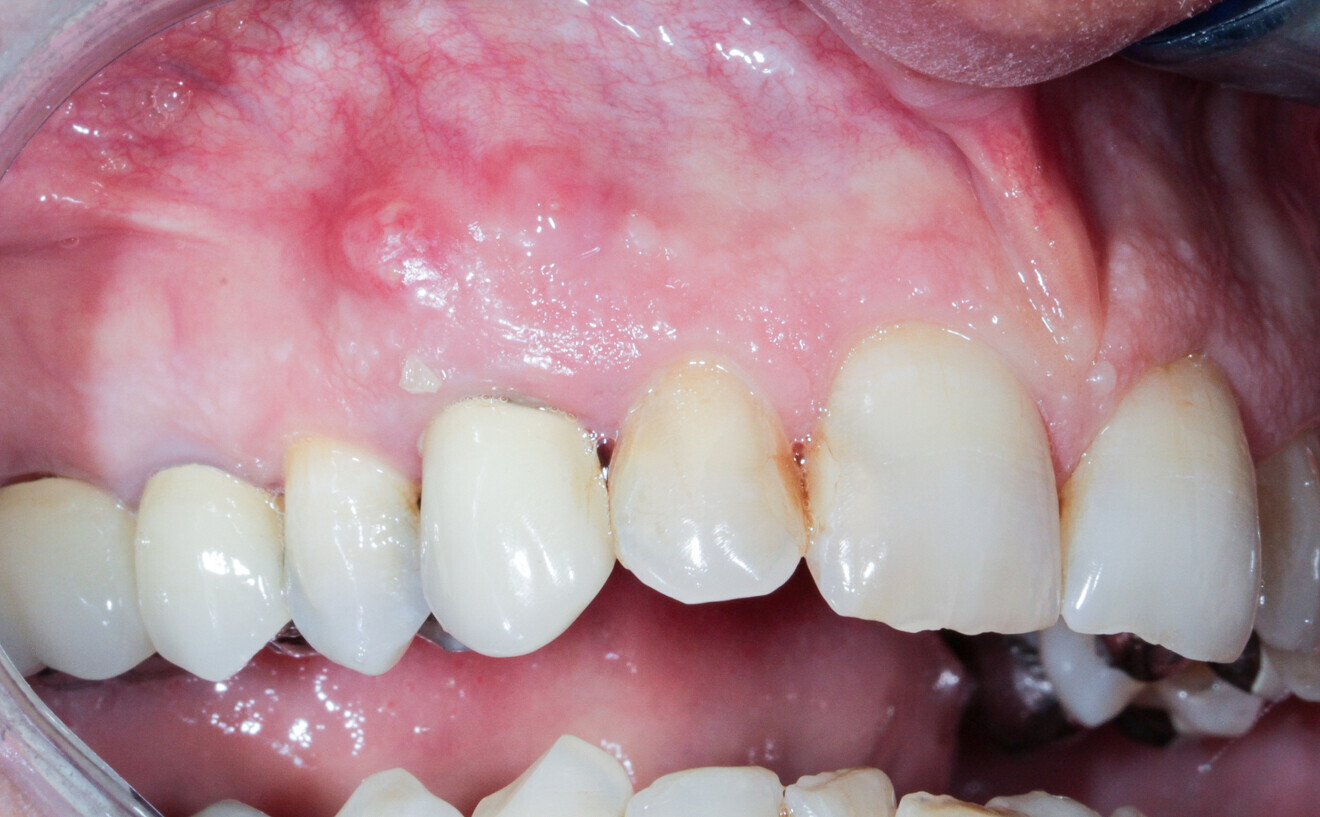

A 62-year-old patient with a bridge from tooth #21 to tooth #27 requiring replacement, teeth #21, 23, 24 and 27 with abutments and the crown of #22, 25 and 26 missing, was treated. The ridge of tooth #22 exhibited a transverse bone insufficiency which would have allowed the placement of an implant, but the aesthetic outcome would have been unsatisfactory (Fig. 10). First, the bridge of tooth #24 was sectioned distally and the root of tooth #27 extracted. After a two-month healing period, the patient was treated with simultaneous extraction, implantation and aesthetic restoration. The bridge was sectioned distally at tooth #21, a full thickness flap was elevated and the teeth #23 and 24 were extracted, allowing the bone defect at tooth #22 to be assessed (Fig. 11). Implants were placed into sites #22, 24 and 27. The root of tooth #23 allowed us to compensate for the bone defect and achieve a satisfactory aesthetic result. The root was prepared as described. The radicular graft was fixated away from the ridge, the edges of the graft in contact with the alveolar bone (Fig. 12). The spaces between the ridge, the graft and the alveoli were filled with a synthetic, hydroxyapatite-based biomaterial, the flap was stretched and sutured around the healing abutments, an impression was taken, and a temporary prosthesis from implant #22 to 27 was made during the day by the laboratory and fitted the same evening. The stitches were removed on the tenth day and the bridge after two months to check for the successful osseointegration of the implants. The osteosynthesis screws were not removed in this case because they were not visible under the gingiva (Figs. 13 & 14). A CBCT assessment was performed after six months to check that the graft had taken successfully. Finally, our colleague fitted the definitive prosthesis.

Fig. 21: Fitting of the definitive prosthesis.